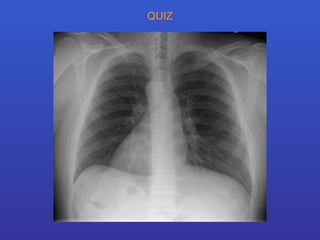

QUIZ